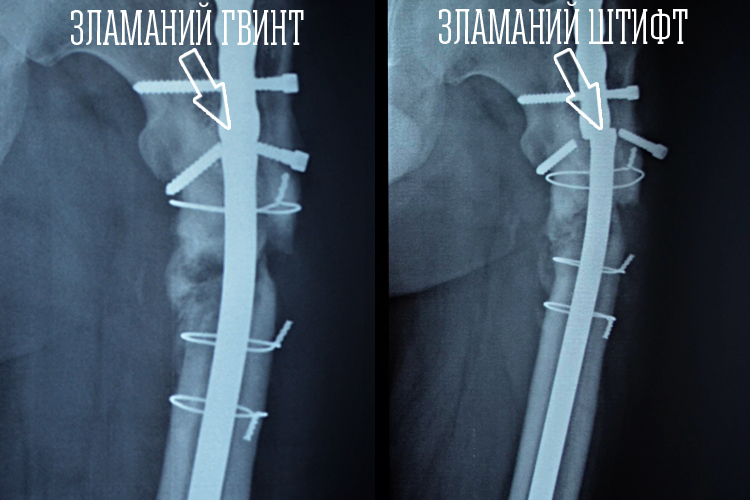

Перші рентгенівські знімки Ігора: на початку зламався гвинт, а потім і сам штифт

Ігор отримав поранення ще влітку 2014 року, коли дивом залишився живим після масивного обстрілу, та ще й зміг самостійно вибрався з оточення з поломаною ногою. Лікувався тривалий час у шпиталях, та кістка так і не зросталася. Навпаки почала розчинятися, а металевий цвях яким все скріпили до купи зламався. Хлопець не міг нормально жити – нога наче б то є, та спиратися не неї неможливо, та ще й болить постійно.